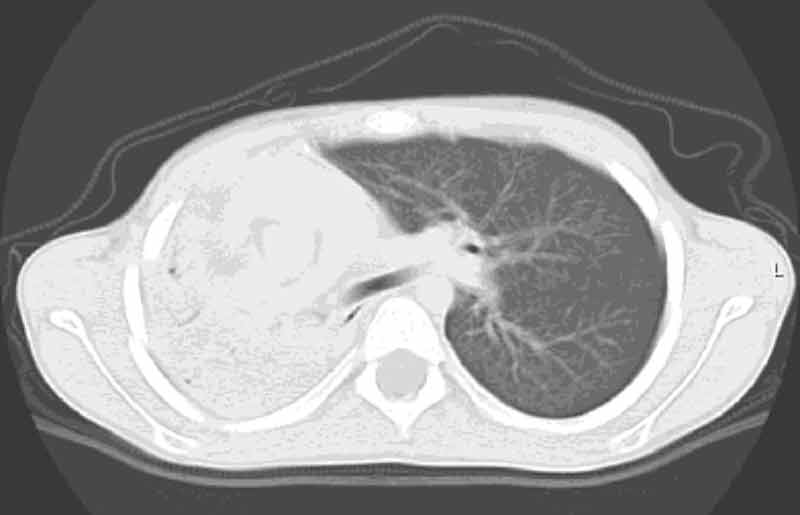

The

CT scan is presented below.

This view is a transverse cut just below the carina.

IS YOUR INTERPRETATION OF THE CT IMAGE?